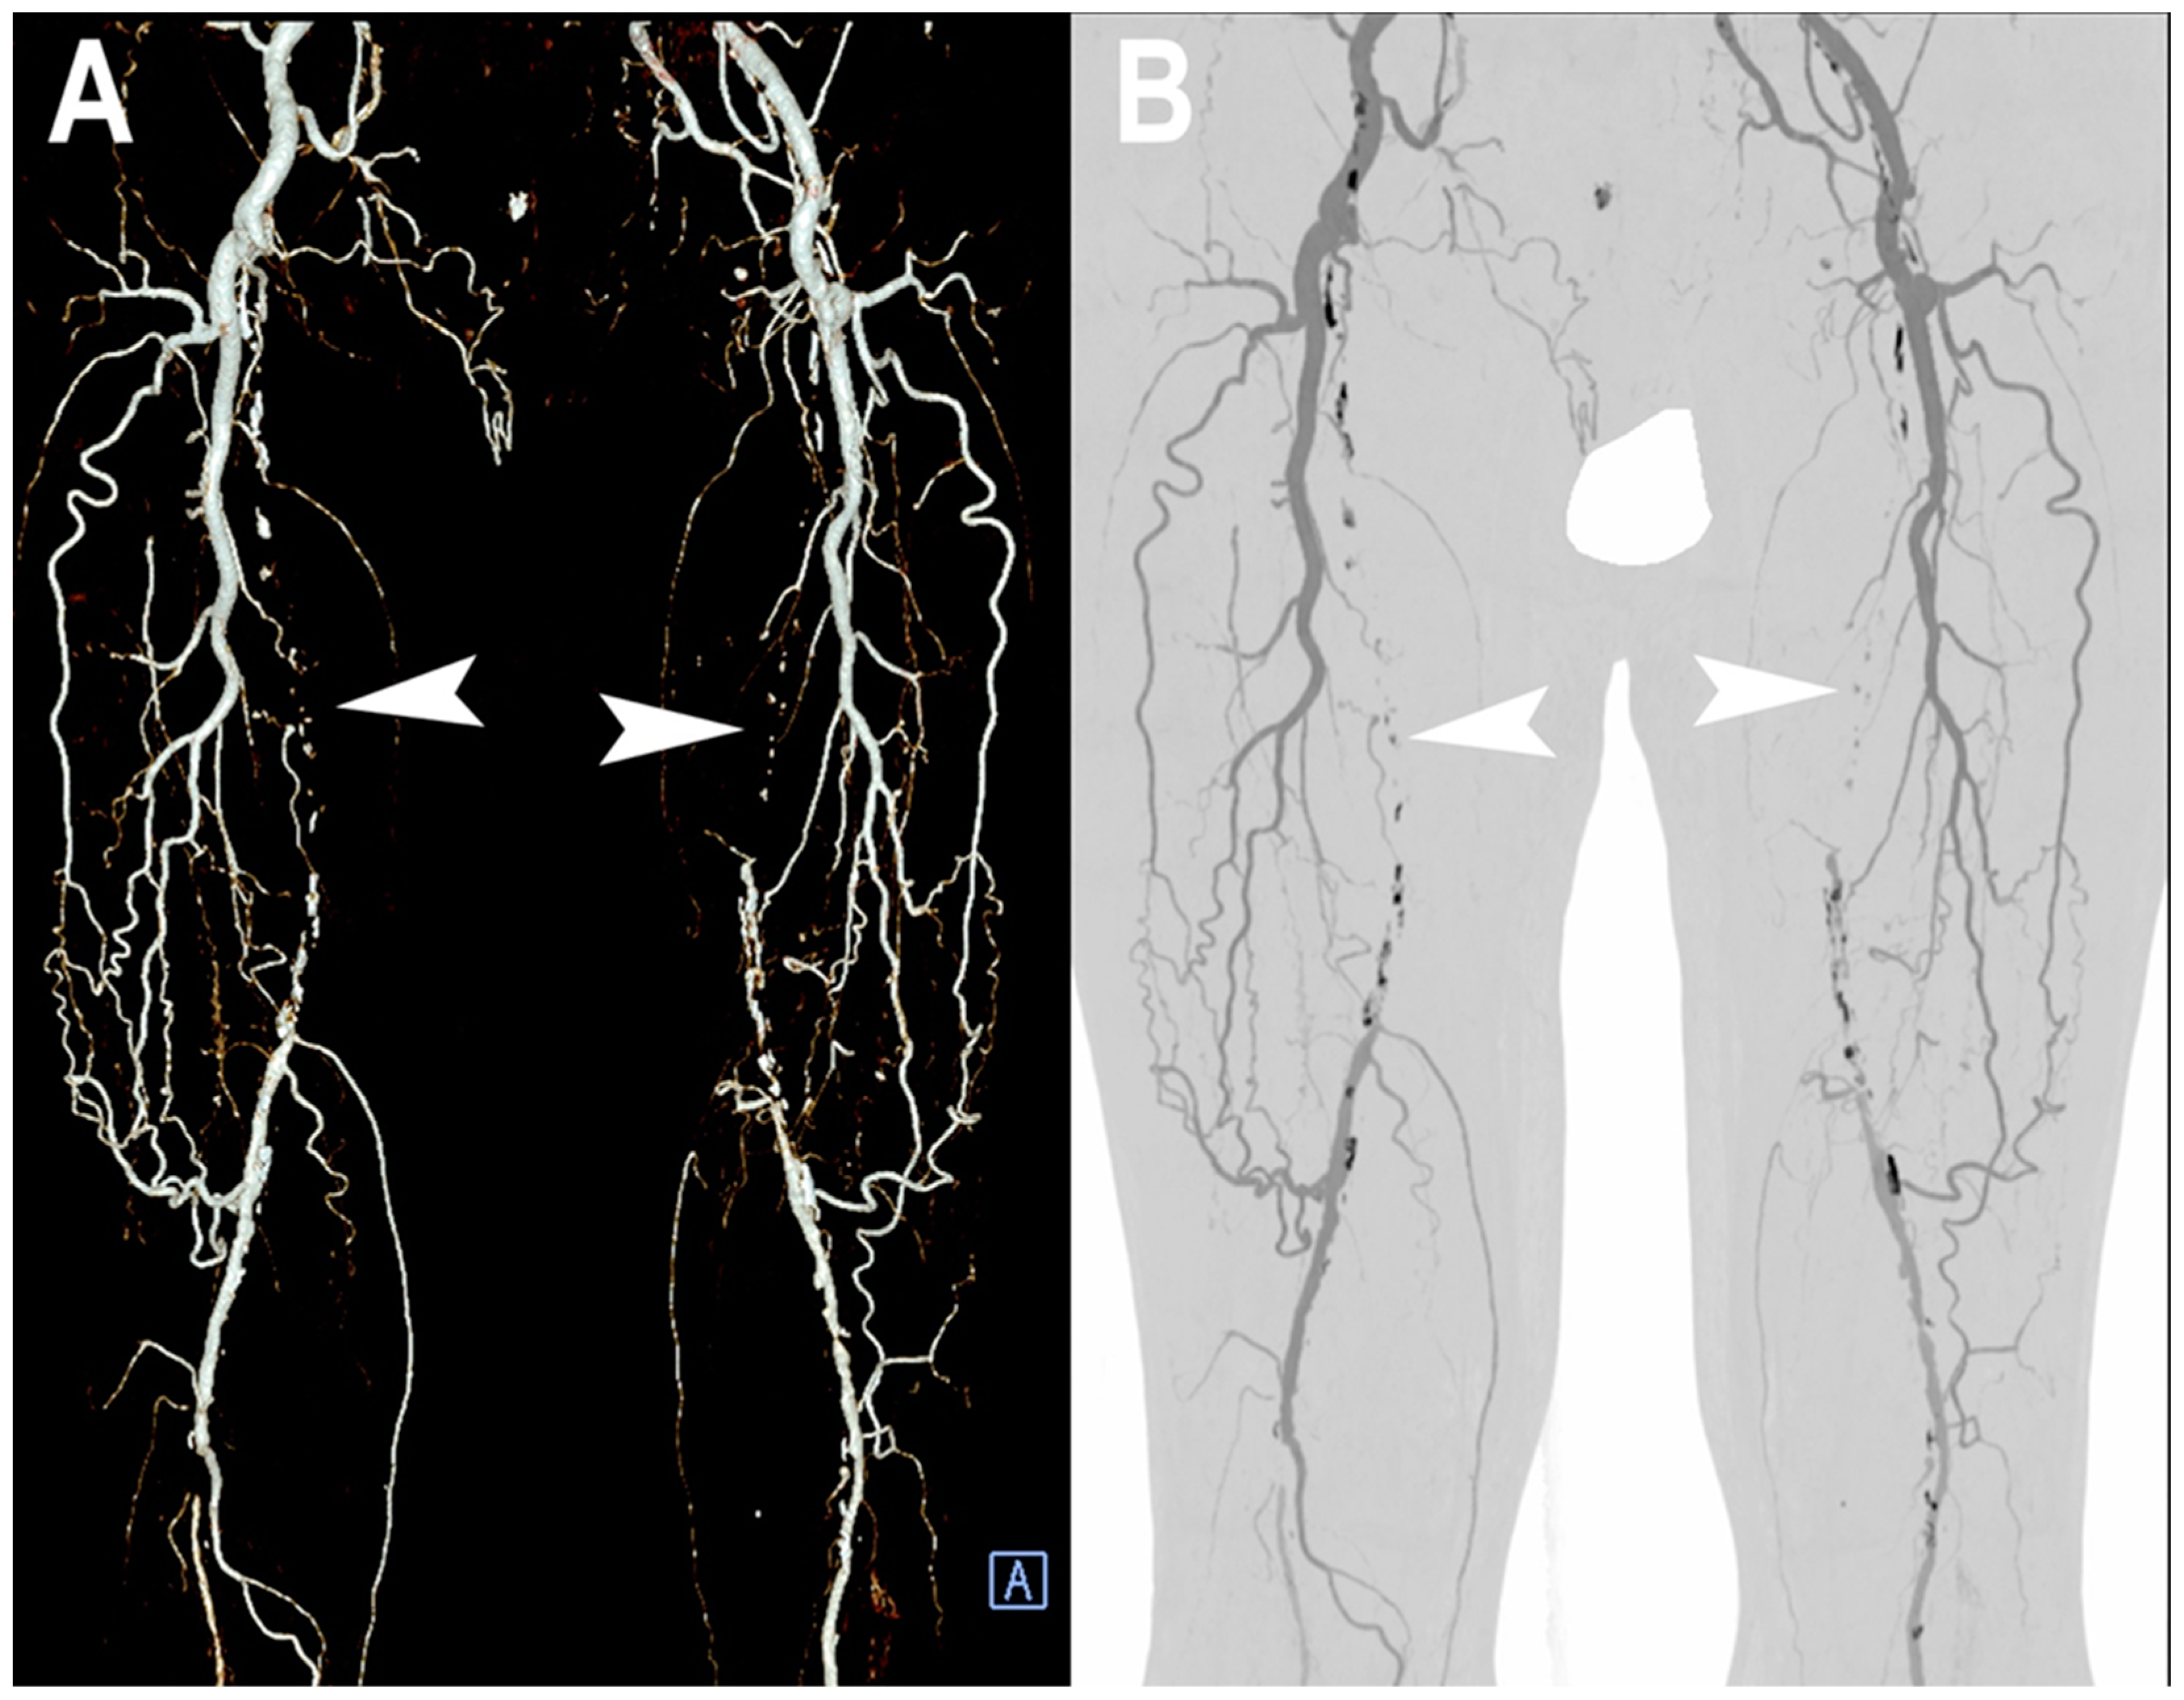

- Shwaiki, O.; Rashwan, B.; Fink, M.A.; Kirksey, L.; Gadani, S.; Karuppasamy, K.; Melzig, C.; Thompson, D.; D’Amico, G.; Rengier, F.; et al. Lower extremity CT angiography in peripheral arterial disease: From the established approach to evolving technical developments. Int. J. Cardiovasc. Imaging 2021, 37, 3101–3114. [Google Scholar] [CrossRef] [PubMed]

- Meyer, B.C.; Werncke, T.; Foert, E.; Kruschewski, M.; Hopfenmüller, W.; Ribbe, C.; Wolf, K.J.; Albrecht, T. Do the cardiovascular risk profile and the degree of arterial wall calcification influence the performance of MDCT angiography of lower extremity arteries? Eur. Radiol. 2010, 20, 497–505. [Google Scholar] [CrossRef]

- Li, Z.; Leng, S.; Halaweish, A.F.; Yu, Z.; Yu, L.; Ritman, E.L.; McCollough, C.H. Overcoming calcium blooming and improving the quantification accuracy of percent area luminal stenosis by material decomposition of multi-energy computed tomography datasets. J. Med. Imaging 2020, 7, 053501. [Google Scholar] [CrossRef] [PubMed]

- Tanaka, R.; Yoshioka, K.; Takagi, H.; Schuijf, J.D.; Arakita, K. Novel developments in non-invasive imaging of peripheral arterial disease with CT: Experience with state-of-the-art, ultra-high-resolution CT and subtraction imaging. Clin. Radiol. 2019, 74, 51–58. [Google Scholar] [CrossRef]